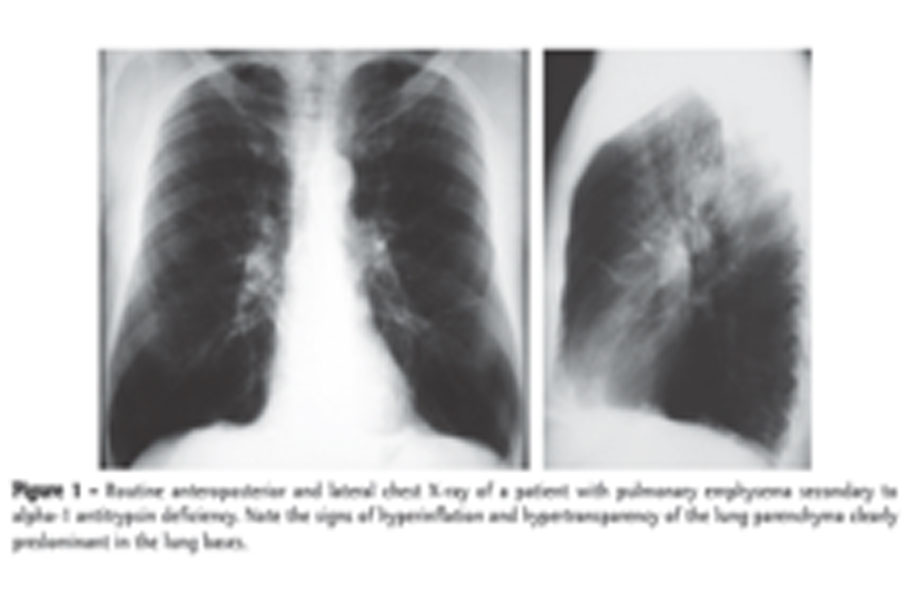

Alpha-1 antitrypsin (a1at) deficiency is a condition in which the body does not make enough of a protein that protects the lungs and liver from damage. The condition can lead to emphysema and liver disease (cirrhosis)

Aat deficiency is a genetic disorder in which abnormally low levels of the protein aat allow certain enzymes to attack healthy tissues, especially the lungs.